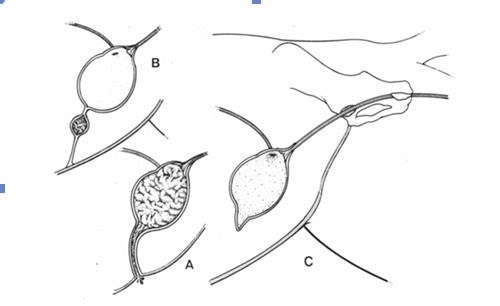

심한 수신증의 경우, 압력으로 인한 신장 실질의 괴사로 조직 손실이 상당히 발생할 수 있습니다. 극단적인 경우, 현저히 확장된 신우를 둘러싸는 얇은 테두리 조직만 남을 수도 있습니다(그림 3). 또한 신문(hilum)에서 신장 피막 쪽으로 뻗는 여러 개의 고에코성 선형 띠가 보일 수 있는데, 이는 신우 사이 격막(interdiverticular septa)을 나타냅니다(그림 3c).